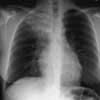

Figure 1

A chest radiograph and sputum evaluation for acid-fast bacteria (AFB) are ordered.

The chest radiographs show alveolar infiltrate in the right upper lobe, with no hilar adenopathy. The cardiac configuration is normal. The sputum shows AFB. These findings in a person with RA who has been treated with infliximab and who has a 3-week history of respiratory symptoms strongly suggest pulmonary tuberculosis, D.